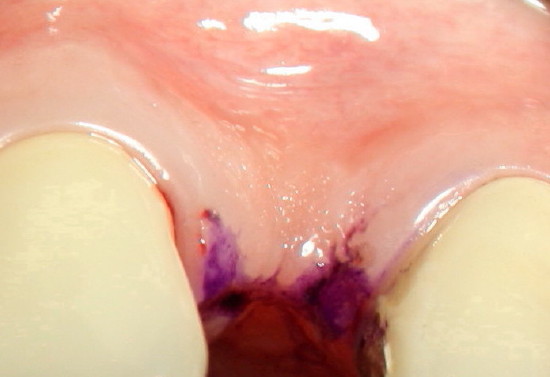

Three weeks post-operatively, a thick band of gingiva with stippling forms in the labial aspect of the implant (between arrowheads in Fig.5, as compared to the gingiva in the edentulous region pre-operatively in Fig.6). In addition, the gingiva is also closing the wound in the lingual aspect the implant (* in Fig.5), back to main article